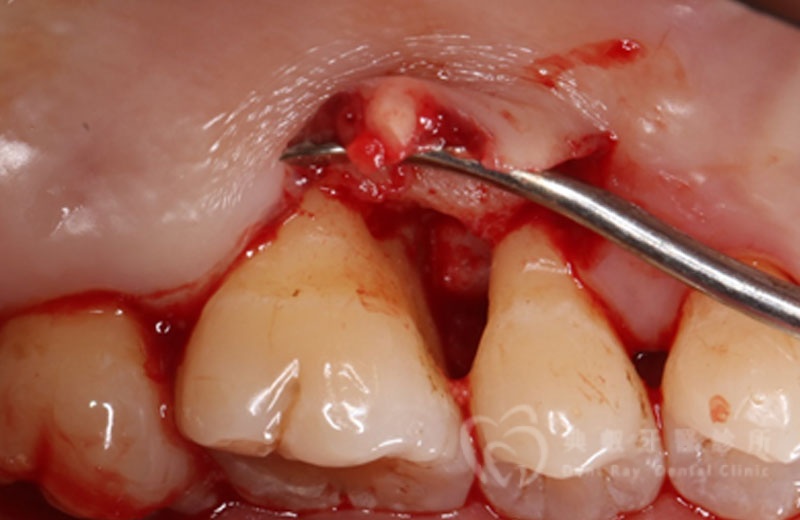

牙周手術案例三

術後六個月